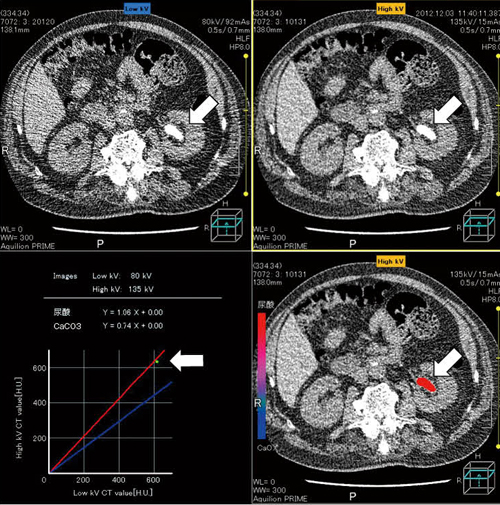

CT値は、水を0 Hounsfield unit(HU)、空気を-1000 HUと定義しており、その値はX線の管電圧で変化する。この管電圧によるCT値の変化の程度は、結石の種類で異なることが知られており、例えば尿酸結石では、高電圧(135~140kV)と低電圧(80kV)のCT値はほとんど差がない(図1)。

図1 放射線透過性結石例(矢印:35mm大の左腎盂結石)  高電圧(135kV)と低電圧(80kV)のCT値にはほとんど差がなく、尿酸結石と推定された(赤の実線)。

高電圧(135kV)と低電圧(80kV)のCT値にはほとんど差がなく、尿酸結石と推定された(赤の実線)。